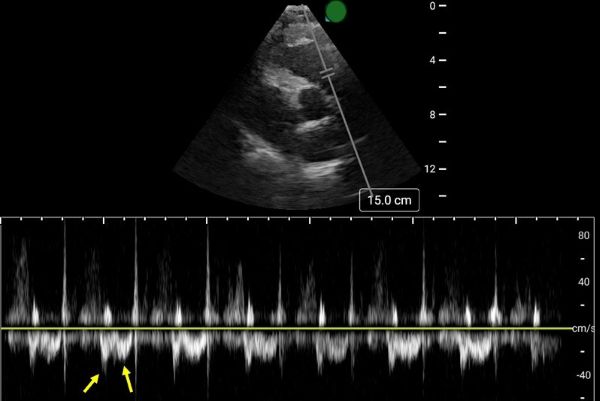

Early Systolic Notching and Pulmonary Embolism

A prospective multicenter study conducted across four academic emergency departments in Turkey evaluated the diagnostic accuracy of early systolic notching (ESN) in emergency department patients. Among the 183 patients included, 52.5% were diagnosed with pulmonary embolism (PE), while 19.7% exhibited the ESN finding. ESN demonstrated a sensitivity of 34% (95% CI: 25–45%) and a specificity of 97% (95% CI: 90–99%) for PE. Sensitivity increased to 69% in patients classified as high or intermediate-high risk. Overall, ESN exhibits moderate to high specificity but low sensitivity, consistent with other sonographic signs of PE. Notably, ESN may also be present in patients with chronic thromboembolic disease secondary to prior pulmonary hypertension.

How to Obtain ESN

To detect ESN, acquire a parasternal short axis view at the base of the heart to visualize the right ventricular outflow tract and pulmonic valve. Position the pulse wave Doppler gate just proximal to the pulmonic valve, with the cursor traversing the outflow tract. ESN is characterized by a sharp systolic spike with a notch, followed by a dome-shaped waveform